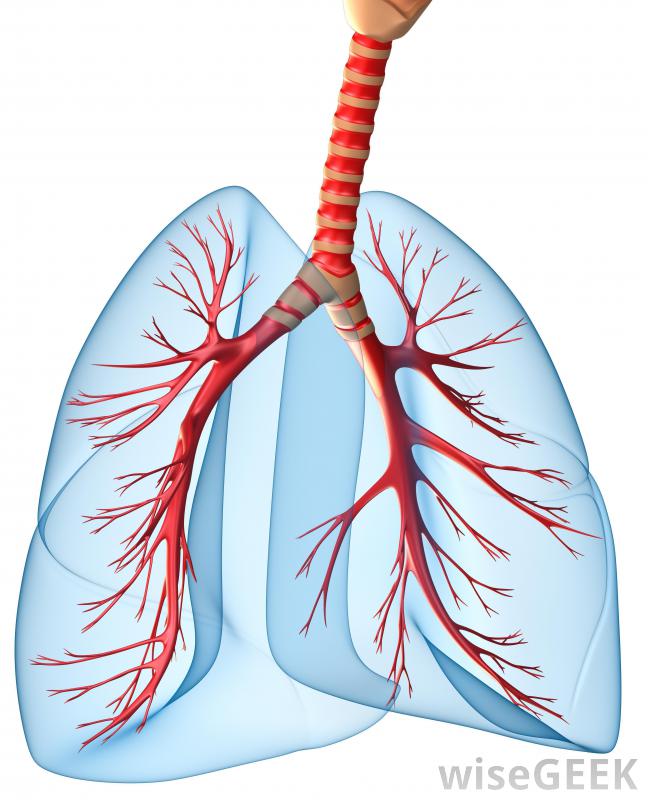

胸膜纖維化是胸膜(覆蓋肺部的組織)發展成纖維組織的一種情況。在正常情況下,胸膜是一種非常柔軟的粘液膜,但當胸膜纖維化發生時,胸膜變厚變硬。纖維生長是良性的,但如果廣泛存在,可能會給患者帶來并發癥,并且可能與對患者有害的疾病過程有關。胸膜纖維化影響覆蓋肺部的組織胸膜纖維化有多種原因,通常與石棉暴露有關,病理學家在嚴重情況下對胸膜進行解剖時,常常發現胸膜中嵌入石棉纖維,有時長達15年,也可能是由炎癥過程、手術創傷或胸腔積液引起的。在輕度病例中,這種情況會導致小面積的纖維組織發育,這可能不會給患者帶來任何問題,并且在胸部x光片上也會發現與此無關的原因將檢查胸部X光片是否有胸膜纖維化的跡象當胸膜嚴重時,整個肺組織會變得很致密,像是很容易膨脹的白色組織當胸膜增厚時,肺不得不更加努力地充氣,最終增厚的組織會損害肺功能,使病人無法呼吸或呼吸極度困難。在這種情況下,受損的胸膜必須手術切除,這樣肺部才能充氣即使是輕度病例,也經常建議進行活檢,以確認生長是良性的,而不是癌癥。病情嚴重的病人會因為呼吸困難而尋求治療。醫生可以通過胸部x光片等工具來診斷病情,對可疑組織進行活檢,并聽肺部的聲音。即使是輕微的病例,也經常建議進行活檢,以確認腫瘤是良性的,而不是癌性的,因為癌癥的治療方法與胸膜纖維化的治療方法大不相同隨著胸膜增厚,肺不得不更加努力地充氣,導致呼吸困難。胸膜中也可能出現胸膜鈣化和胸膜纖維化鈣化,胸膜上出現小的白色斑塊。在輕度病例中,這些斑塊可能沒有問題,但如果它們變大、擴散,或與廣泛的胸膜纖維化相關,則可引起關注纖維化也可能發生在臟器周圍的粘液膜上,例如心臟和腸道。病理學家經常在胸膜中發現石棉纖維,以防接觸導致胸膜纖維化。